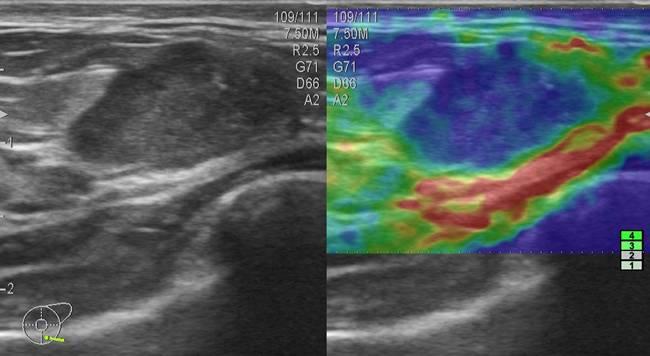

Ung thư vú - Ảnh 3

Ung thư vú

» Thông tin: Nữ giới – 33 tuổi.

» Lâm sàng: Khối tuyến vú.